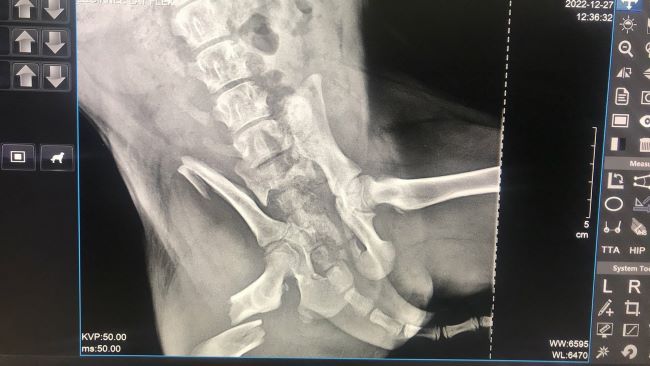

Поняла, что дело плохо. Долго искать не пришлось, щенок лежал под бетонной плитой. Не сразу поняла, что с ним. Крови не было, внешне целый. Когда попыталась его вытащить, тогда и поняла, что его задняя лапа висит как плеть. Срочно повезла в ветклинику, малыш плакал всю дорогу и продолжает до сих пор, - рассказывает Наталья Филиппова. - В клинике сделали рентген, и он показал сложный перелом с защемлением. Ортопеда не было на месте, нас отправили домой, сказали приехать на следующий день и сообщили, что операция будет стоить примерно 18 000 рублей, возможно, потребуется не одна операция. Я впала в ступор, не понимаю, из чего складываются подобного рода суммы за операцию, но малышу больно, и он хочет жить. А значит, ему нужно поскорее помочь.